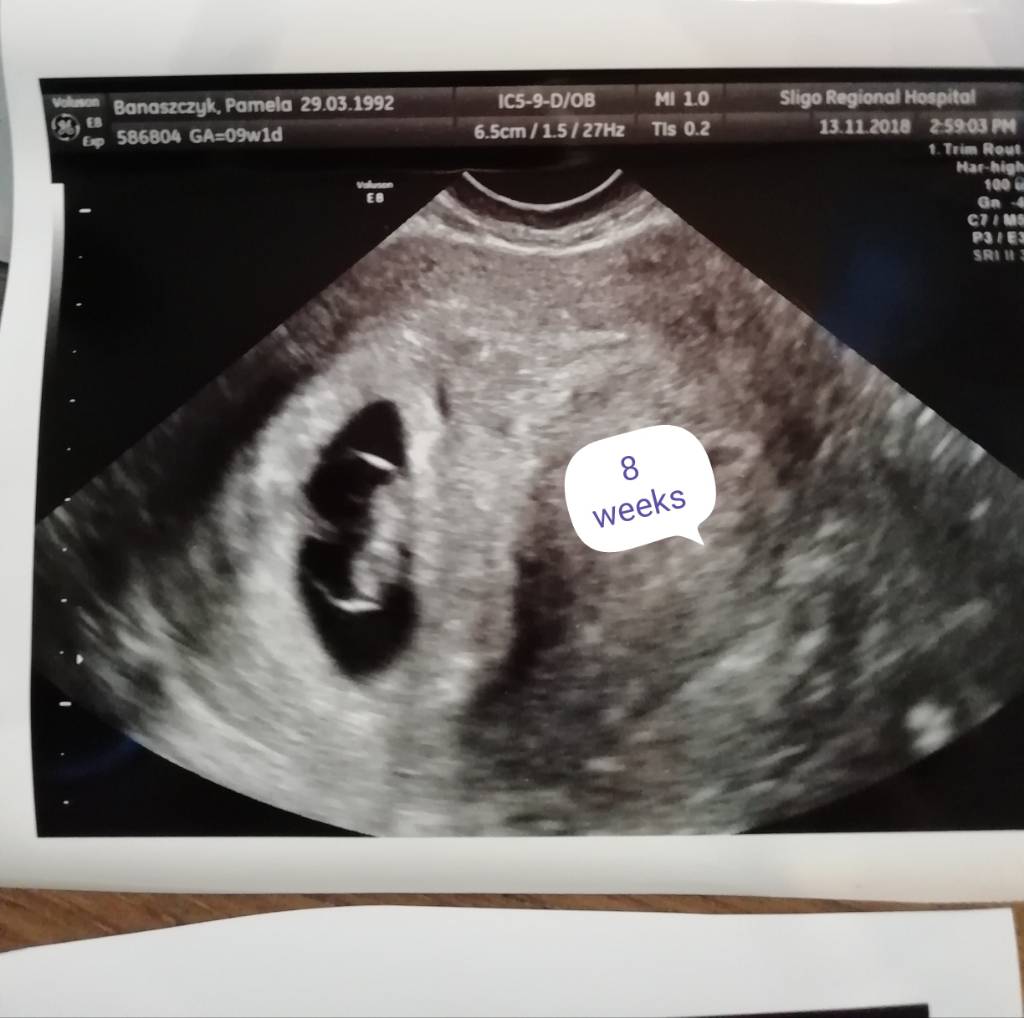

Jaki cudowny widok. Dzidzia taka duża już się wydaje. Gratulacje!Usg z wczoraj 8 tydzień Zobacz załącznik 916548